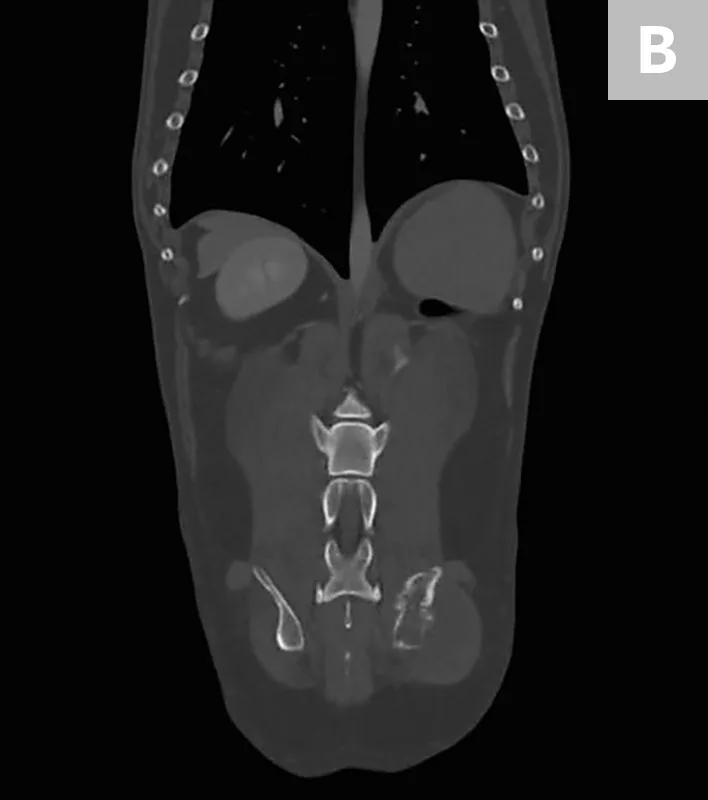

Featured Image

FIGURE 2

Axial CT images showing a large mass arising from the right ilium with a significant soft-tissue component in both the inner and outer tables of the pelvis

Because the lungs are the most common site of metastasis in cases of chondrosarcoma, staging was determined via bone scan and chest CT, which confirmed that there were no other sites of disease. Staging was determined to be Enneking Stage IB; prognosis was good overall. Core needle biopsy confirmed low-grade chondrosarcoma.